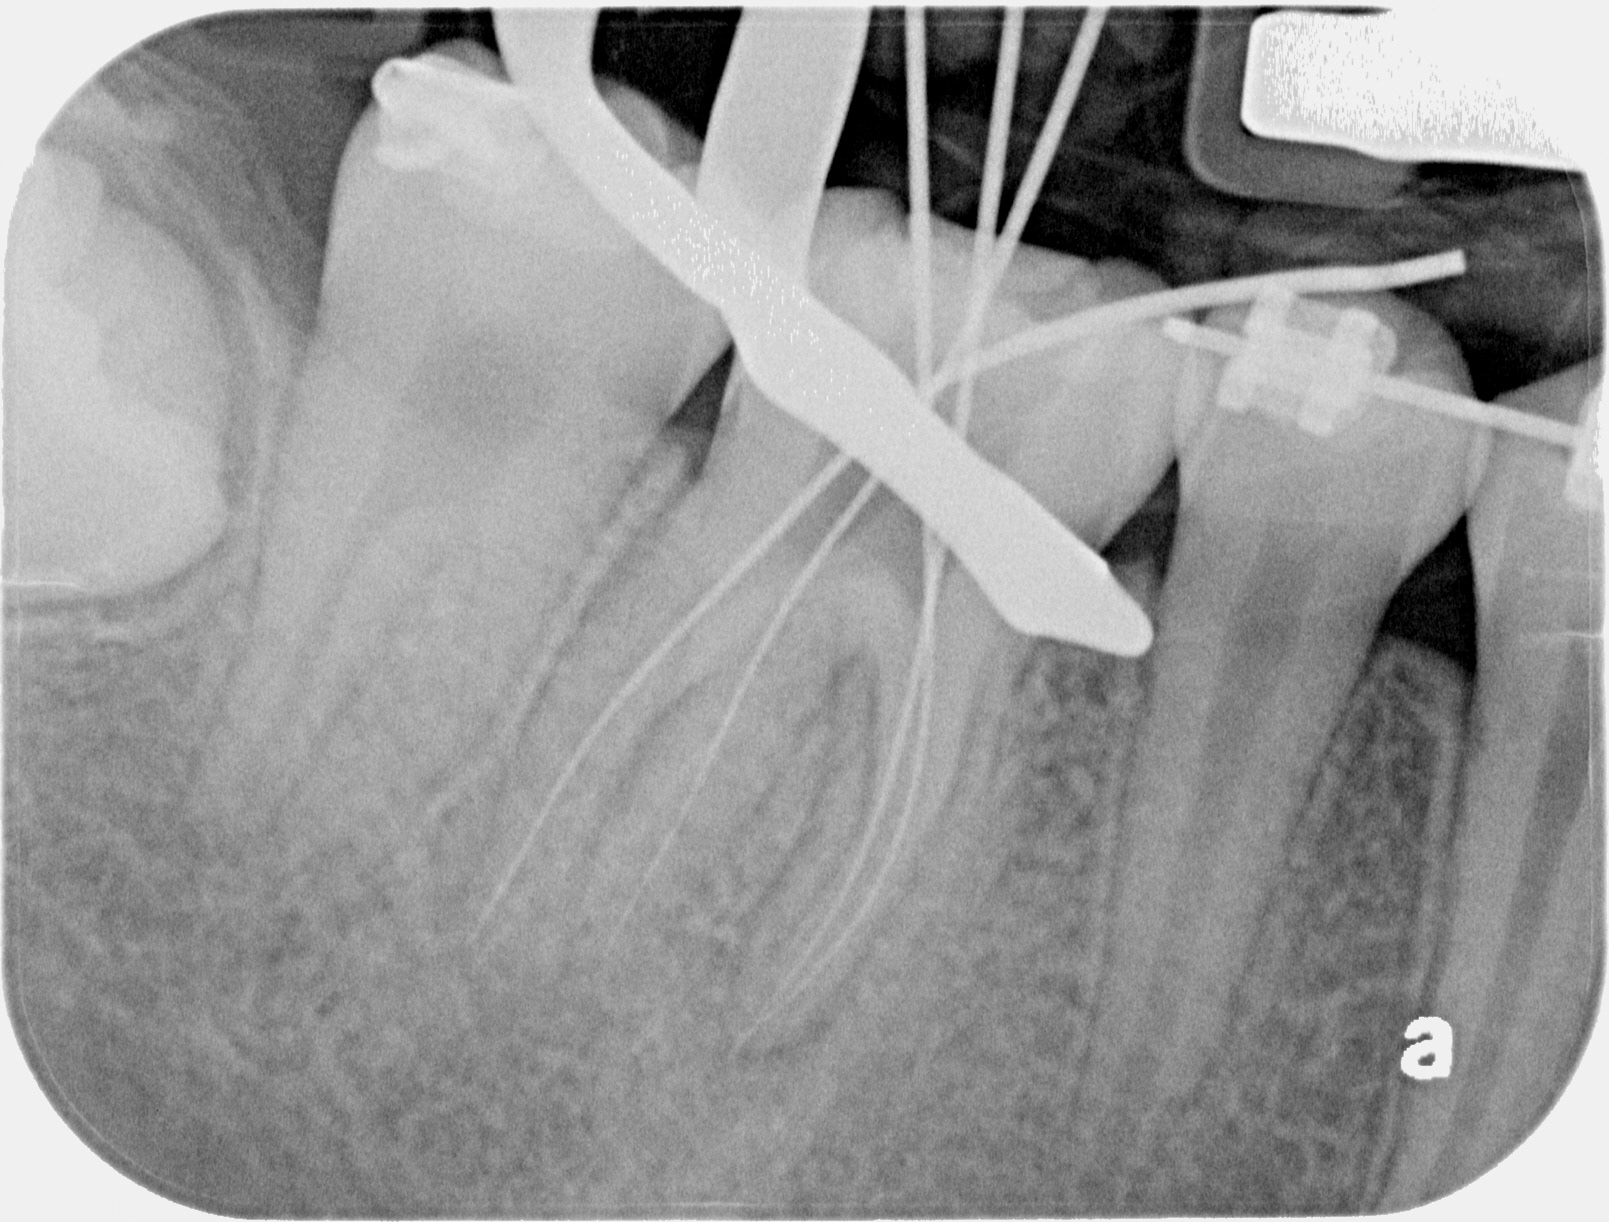

WORKING LENGTH